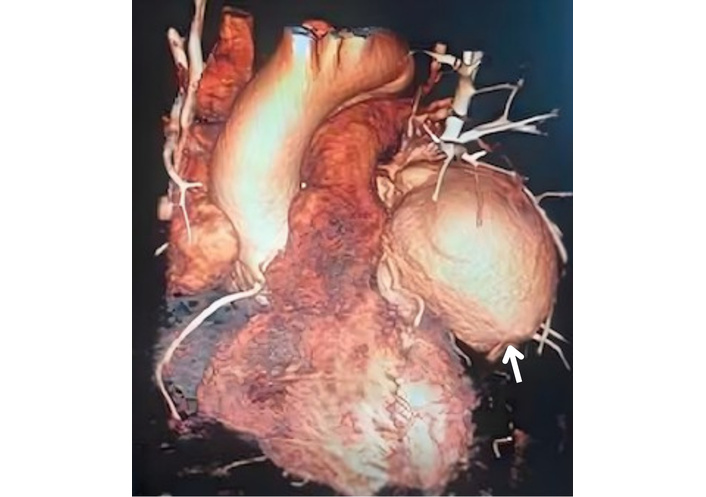

A TTE evaluation performed three months later did not report the mass seen on CXR as a possible pseudoaneurysm (Figure 4). The mass on the left side became more prominent on CXR (Figure 5), nineteen months later. A thoracic CT scan revealed a giant pseudoaneurysm on the posterior wall of LV which was 10 cm × 7 cm in size (Figure 6). The patient was urgently transferred to our center for definitive management, where a coronary angiography (CA) was performed. CA showed normal coronary anatomy (Figures 7 and 8), but left ventriculography confirmed the diagnosis: leakage of contrast medium into the pseudoaneurysm sac was clearly observed (Figures 9 and 10).

Thoracic CT imaging shows a left ventricular pseudoaneurysm (arrow). CT: computed tomography.